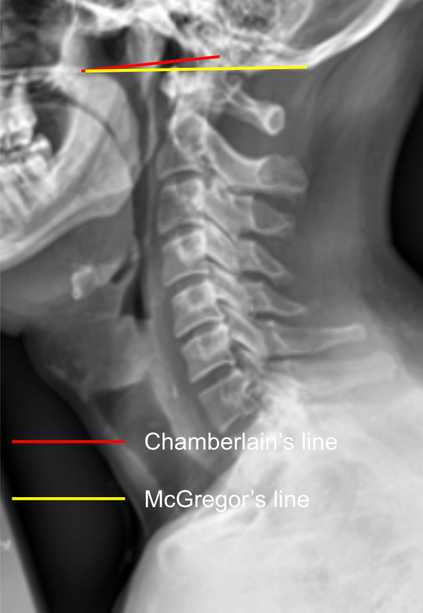

Chamberlain’s Line and McGregor’s Line are radiographic reference lines used to assess the position of the odontoid process (dens) relative to the skull base, helping identify basilar invagination or craniovertebral junction anomalies.

• Chamberlain’s Line: Drawn from the posterior edge of the hard palate to the posterior margin of the foramen magnum (opisthion).

• McGregor’s Line: Drawn from the posterior edge of the hard palate to the most caudal point of the occipital curve (inferior occipital surface).

The vertical distance of the dens tip above these lines indicates upward migration of the odontoid into the cranial cavity.

• Use a neutral lateral cervical spine X-ray (as shown in the provided image).

• Chamberlain’s Line: From posterior hard palate → opisthion

• McGregor’s Line: From posterior hard palate → most caudal occipital point

Measure the vertical distance (in mm) from the tip of the odontoid to each line:

• Positive value = dens projects above the line

• Negative value = dens lies below the line

• Normal Chamberlain’s line: Dens ≤ 3 mm above line

• Pathologic Chamberlain’s/Suggestive of basilar invagination: Dens > 3-5 mm above line

• Normal McGregor’s line: Dens ≤ 4.5-5 mm above line

• Pathologic McGregor’s/ Suggestive of basilar invagination: Dens > 4.5-5 mm above line

McGregor’s Line is more reproducible radiographically since the opisthion can be difficult to visualize on plain films.